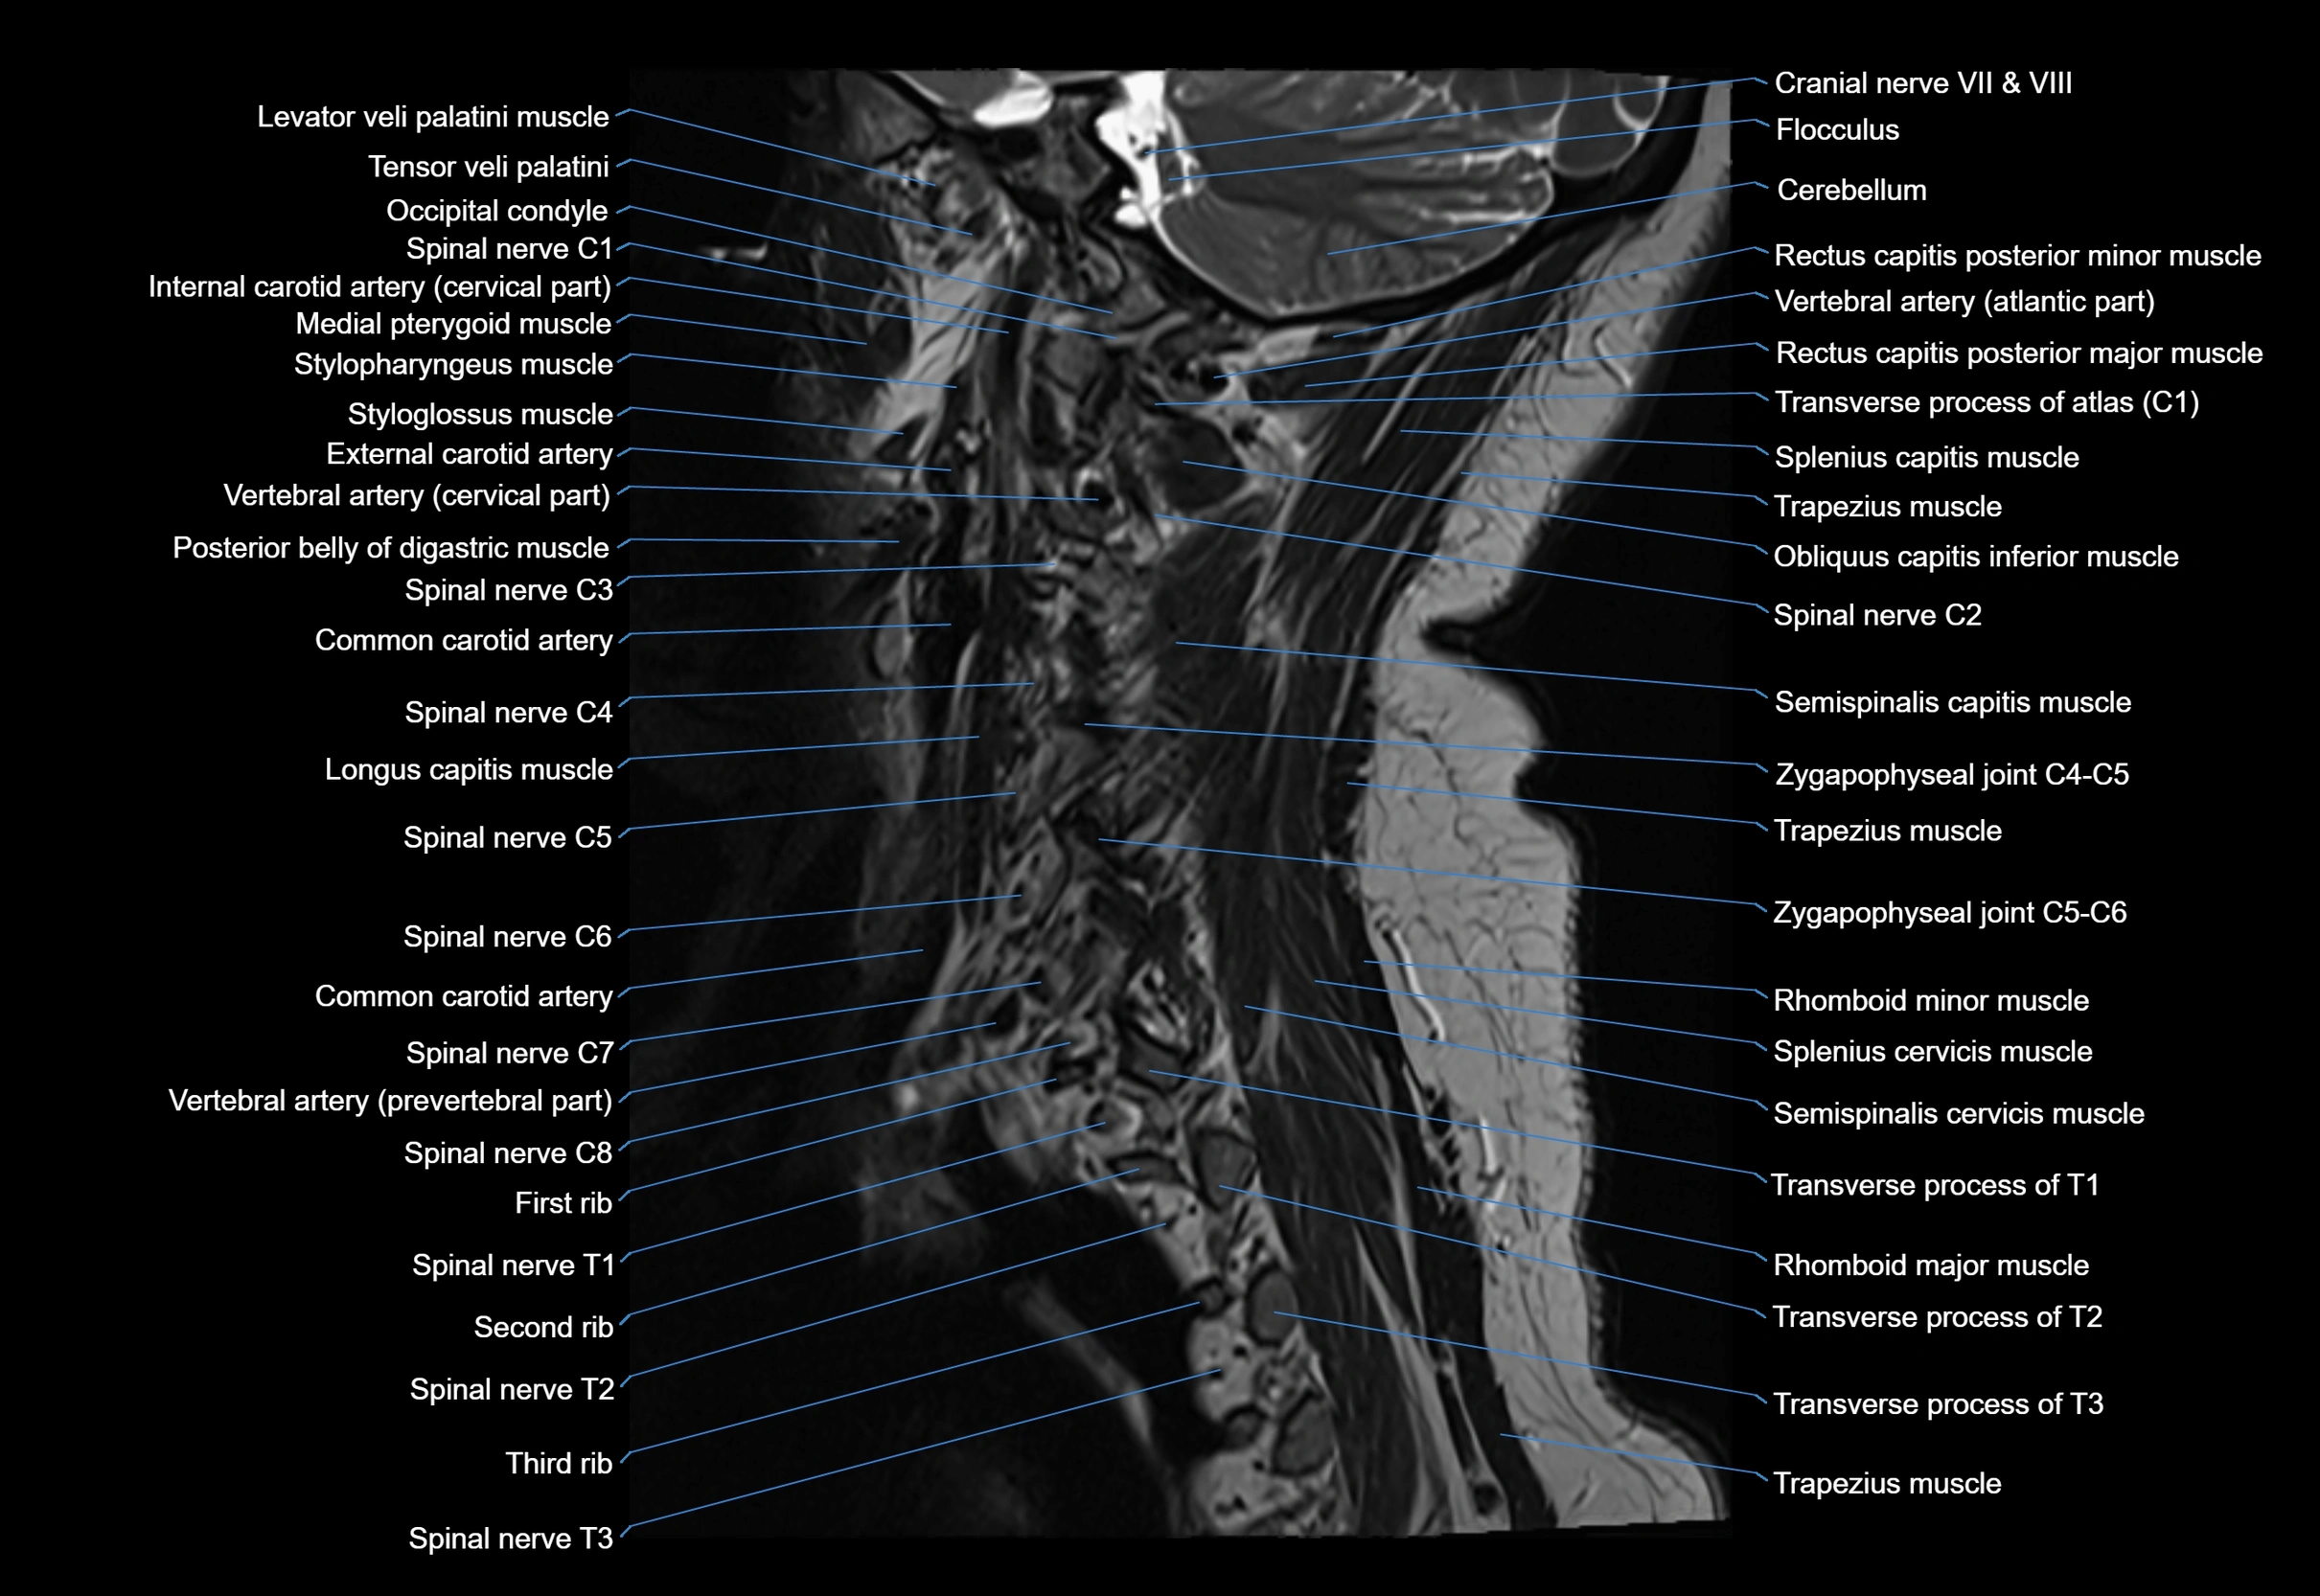

MRI image

image